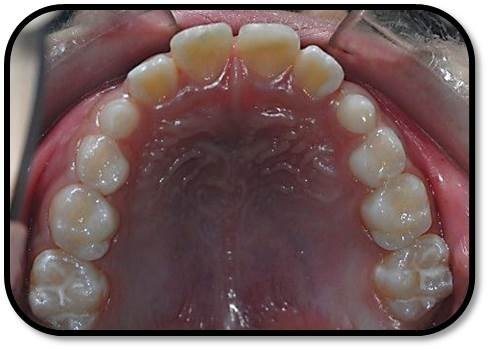

临床检查 患儿自主进入诊室,神志清。面部对称。 11:冠中1/3横折,折断面见玻璃离子充填材料覆盖,叩痛(+),松动IO,龈无异常,冷测同正常对照牙。11、21、31、41无咬合创伤及颌干扰。X线:11冠中1/3横折,远中髓角仅极薄层牙本质覆盖,11发育9期,根尖孔未完全闭合,未见明显根折线,根周膜清晰。 21近中切角折断,断面见玻璃离子充填材料覆盖,叩痛(-),不松动,龈无异常,冷测同正常对照牙。X线:21近中髓角薄层牙本质覆盖,21发育9期,根尖孔未完全闭合,未见明显根折线,根周膜清晰。 12、22、31、32未见异常,叩痛(-),不松动,龈无异常。 65MO、84DO龋洞,叩痛(-),不松动,龈无异常。 既往史 :否认特殊 家族史:否认特殊

诊断: 11、21冠折牙本质暴露 65MO、84DO深龋 治疗计划: 1. 口腔卫生宣教,嘱近期勿用前牙咬物,勿食过冷过热食物刺激牙髓。 2. 11、21两周复查牙髓活力,一月后牙髓无异常,11行断冠再接,21树脂修复切角恢复外形。成年后全冠修复。 3. 定期复查,牙髓活力及根尖孔发育,不适随诊 4. 65MO、84DO充填 当天处置: 1、口腔卫生宣教,嘱近期勿用前牙咬物,避冷热刺激。 2、11、21两周复查牙髓活力,不适随诊。断冠交患者保存在生理盐水中,不适随诊,必要 时行根尖诱导成形术。 3、65MO、84DO充填 治疗过程: (两周后)复诊:无不适,充填无脱落 查: 11GIC充填完好,叩痛(-),冷测一过性敏感,不松动,龈无异常。 21GIC充填完好,叩痛(±),冷测同正常对照牙,不松动,龈无异常。 X线:11、21发育9期,根周膜清晰。 牙面软垢菌斑大量。 处置:1、口腔卫生宣教,嘱近期勿用前牙咬硬物,避冷热刺激。 2、一月后行断冠粘接(断冠交患者保存在生理盐水中),不适随诊,必要时行根尖诱 导成形术。。 (1个月后)复诊:无不适 检查:11、21GIC充填完好,叩痛(-),冷测同正常对照牙,不松动,龈无异常。 处置:1、口腔卫生宣教 2、11清洁牙面,去部分GIC,one-coat bond+纳米树脂(A2)行断冠粘接(断冠 舌侧备排溢道,唇侧备洞缘斜面),调牙合,抛光,嘱勿用前牙咬硬物。 3、21清洁牙面,去部分GIC,备洞缘斜面,磷酸酸蚀one-coat bond+纳米树脂(A2) 修复切角缺损,调牙合,抛光,嘱勿用前牙咬硬物。 4、三个月后复诊。

随访复查: 治疗后5个月复查:上前牙偶遇冷热敏感。 检查:11牙面软垢菌斑大量,龈缘略红肿,断冠粘接处完好,叩痛(-),不松,龈未见异 常,冷测敏感一过性。 21充填完好,叩痛(-),不松动,冷测敏感一过性。 X线:11、21牙根继续发育,根周膜清晰,未见明显牙根吸收。 处置:1、口腔卫生宣教,嘱注意清洁牙面。2、11清洁牙面,抛光。嘱勿用前牙咬硬物,避冷热刺激。 治疗后9个月复查: 上前牙偶遇冷热敏感,一过性,否认自发痛 ,咬合痛。 检查:11断冠粘结处完好,21树脂充填体完好边缘密和,未及龋洞,叩痛(-),不松,龈 未见异常,冷测敏感一过性。牙髓电活力测12:25、26、31 ;11:37、36、37 ; 21:42、42、34 ;22:39、40、36;X线:11、21牙根发育完成,根周膜清晰,未 见明显牙根吸收。 12、22叩痛(-),不松,龈未见异常,冷测正常。 口腔卫生一般,牙面软垢菌斑中量。 处置: 1、口腔卫生宣教,嘱注意清洁牙面。 2、嘱半年后复查。